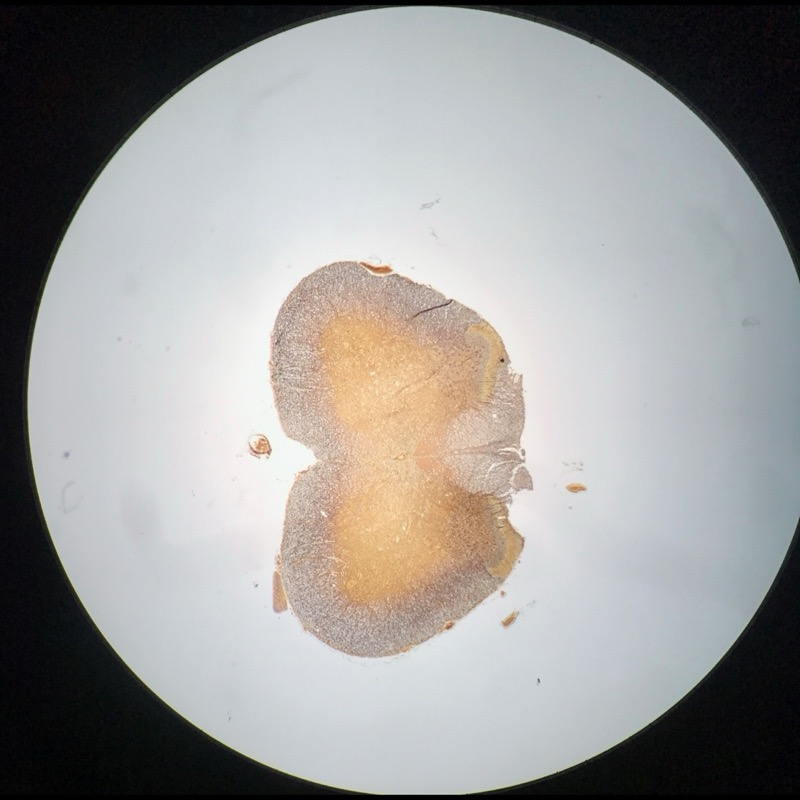

| 1:8:5 | Medulla Spinalis Galiomycin/Azan | ![]() ![]() ![]() ![]() |

| 1:8:6 | Medulla spinalis, silverfärning | ![]() ![]() ![]() ![]() ![]() ![]() |